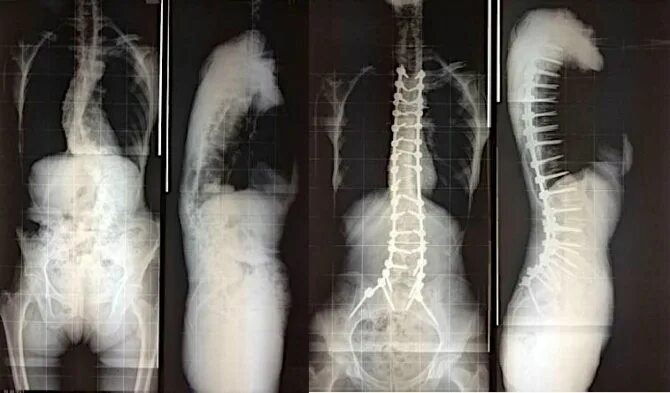

Сколиоз 4 степени инвалидность